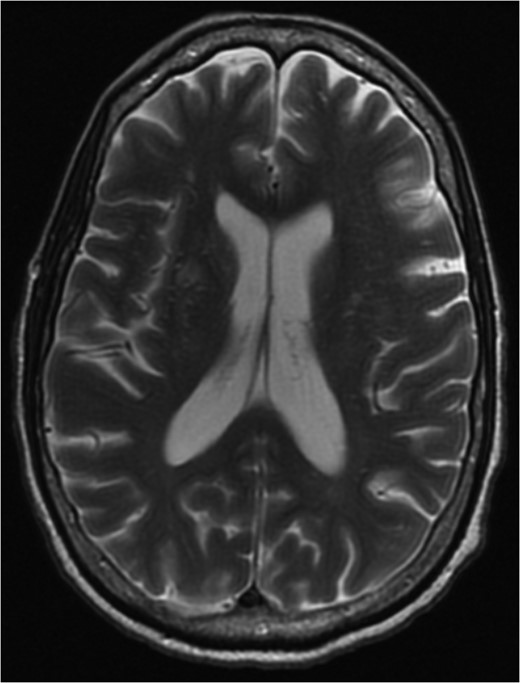

MRI brain at the time of diagnosis, Axial T2 sequence. Vasogenic edema involving the bilateral cerebral hemispheres, with relative sparing of the frontal lobes suggestive of PRES. Pneumocephalus is present secondary to interval placement of an external ventricular drain (seen in the right lateral ventricle).